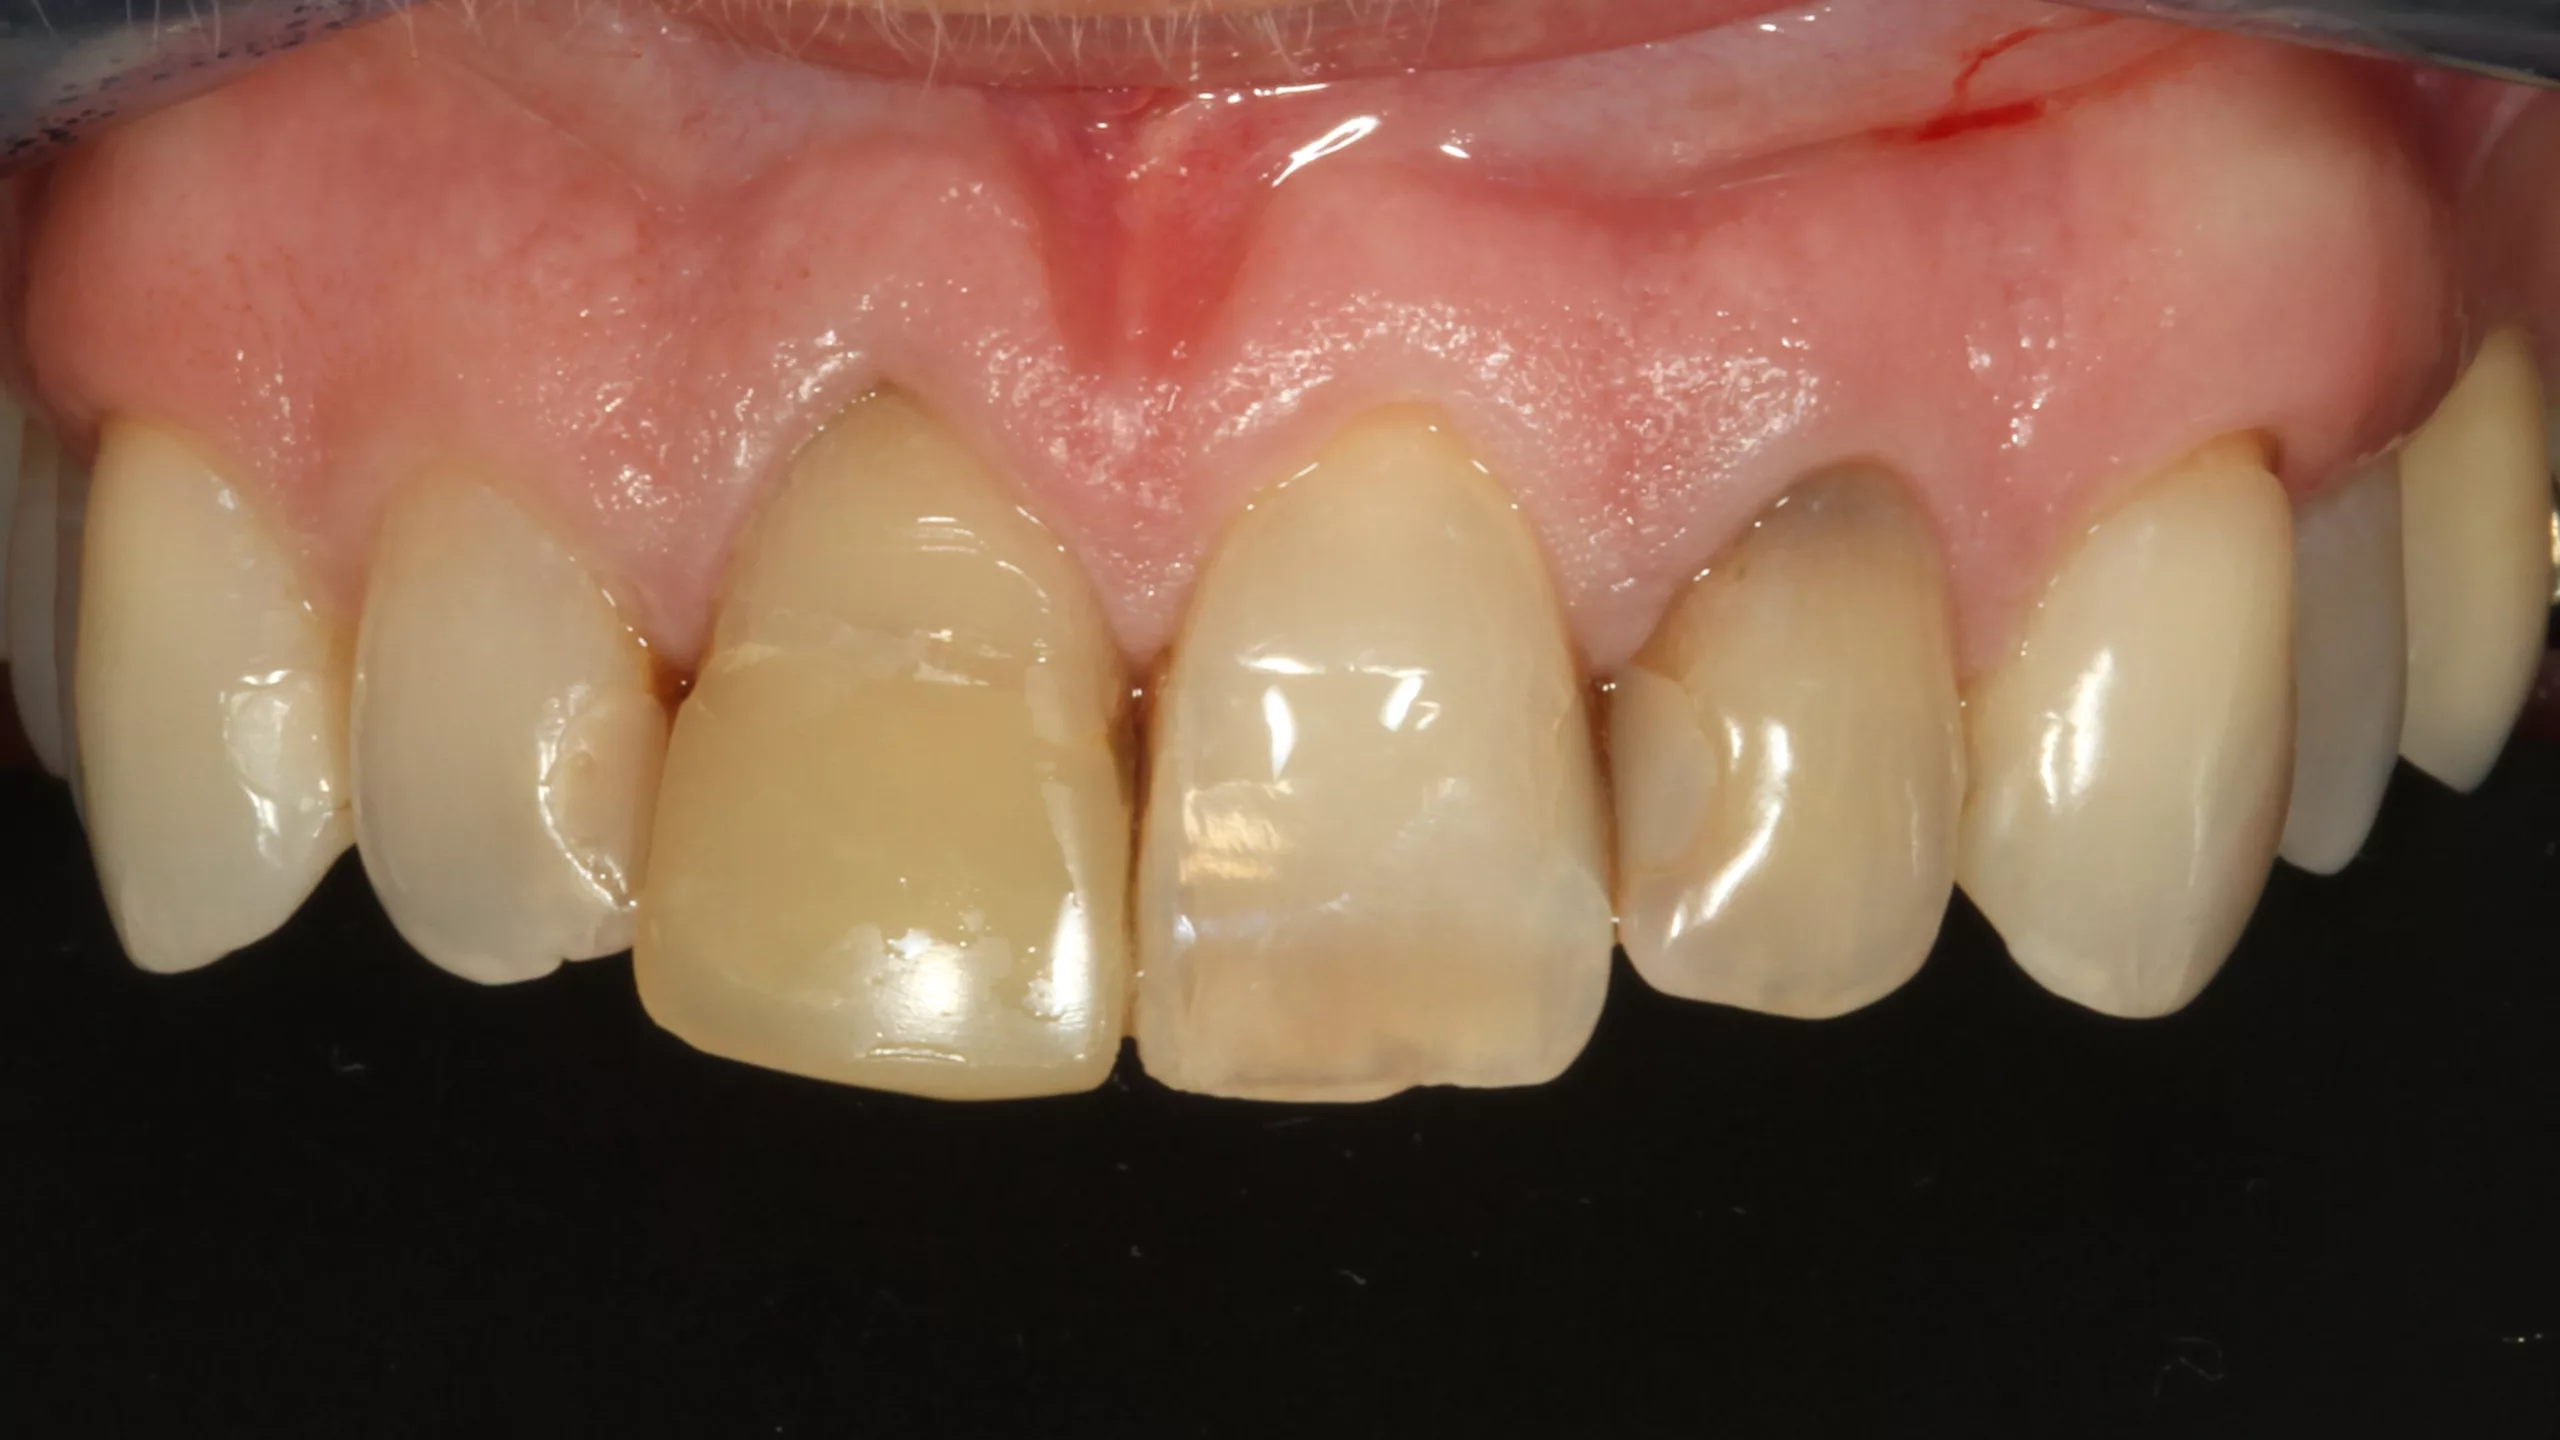

Bei der 55-jährigen Patientin bestand der Wunsch nach einer ästhetischen Neuversorgung ihrer Frontzahnsituation (Abb. 29 und 30). Die Zähne 11 und 22 waren wurzelkanalbehandelt, alle Schneidezähne wiesen ältere, große, farblich nicht mehr passende Kompositversorgungen auf. Die Neuversorgung wurde aufgrund der Stabilität und der besseren Abdeckung verfärbter Zahnbereiche aus einem monolithischen Zirkonmaterial gefertigt, die labial additiv verblendet wurden (Abb. 31 und 32).